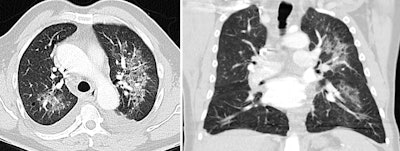

In this case of atypical pulmonary edema, predominant left-sided edema is due to acute mitral valve rupture with eccentric regurgitation seen at echocardiography. Bilateral pleural effusion is also seen. All images courtesy of Dr. Juan Arenas-Jiménez, PhD.

An 89-year-old woman presented with dyspnea and elevated D-dimer. Cardiomegaly and marked elevated proBNP suggested the diagnosis of unilateral pulmonary edema that resolved after diuretic treatment. D-dimer levels are elevated in most patients with acute thrombosis, but the levels also are increased in advanced age, after surgery, during pregnancy and puerperium, with cancer and other chronic inflammatory conditions, and in many other disorders. D-dimer elevation is the cause of request for many CT angiograms that finally reveal an alternative diagnosis causing dyspnea.On drug toxicity, the group suggests always bearing in mind treatment-related reactions, especially in patients with neoplasms, connective tissue, and transfusions. These reactions can appear in recently initiated or long-standing treatments.